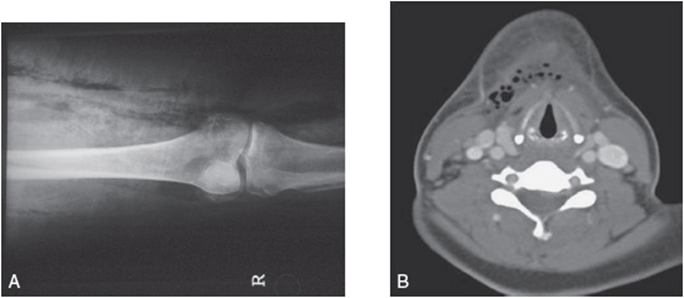

Imaging studies may be useful but only in those instances where the patient is not decompensating and the diagnosis remains equivocal. Plain radiographs may show gas within soft tissues, although this is only present in one third of patients and a negative study cannot rule out NSTI. There are some data that suggest CT scans, with or without contrast, may be helpful in identifying characteristic features of NSTIs such as soft tissue gas and inflammatory changes. Although CT scans may have a role in diagnosing NSTIs, this has not yet been adequately studied. MRI has been shown to have a sensitivity of 90% to 100% in diagnosing NSTIs, but a specificity of only 50% to 80%. Because MRIs take such a considerable amount of time to obtain, the risks associated with delaying treatment drastically limit the utility of MRI in the evaluation of NSTIs. For examples of imaging studies that demonstrate NSTIs, see Figure 45-2.

Figure 45-2. Radiographic evidence of necrotizing soft tissue infections. (A) Plain radiograph that demonstrates gas in the soft tissue of the right lower extremity. (Courtesy of Susan Dufel, MD.) (B) CT scan demonstrating gas within the soft tissue of the neck as well as fat stranding that crosses fascial planes. (Reproduced, with permission, from Tintinalli JE, Stapczynski JS, Ma OJ, et al. Tintinalli’s Emergency Medicine. 7th ed. New York: McGraw-Hill; 2011. Figure 241-5.)